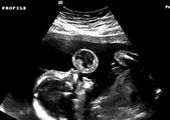

Niesamowite zdjęcia USG. Nawet lekarze byli zaskoczeni

Badanie USG to zwykle jeden z najbardziej wyczekiwanych momentów w czasie ciąży. Jesteśmy ciekawi, jak będzie wyglądać nasze dziecko, jaki będzie miało kształt nosa czy uszu. Czasem jednak zamiast radości, zdjęcie USG może stać się powodem niepokoju i stresu. Tak było w przypadku Jade Boyland z Somerset w południowo-zachodniej Anglii, która na swoim pierwszym badaniu USG ujrzała twarz swojego dziecka. Była przerażona, ponieważ zobaczyła zarys zgarbionego malucha, z wielkimi oczami i wydłużonymi palcami, które przypominały szpony. Jade przyznała, że gdy pierwszy raz zobaczyła twarz swojego malucha, nazwała "demonicznym dzieckiem". Początkowo żartowała z tego, jednak wraz z biegiem ciąży coraz bardziej przejmowała się kwestią wyglądu córki po porodzie. Niepokój jednak okazał się zbyteczny, ponieważ urodziła piękną, zdrową córeczkę, która obecnie ma 9 lat. Po "demonicznym wyglądzie" nie ma żadnego śladu. Jednak, jak twierdzi mama, córka ma "demoniczny charakter" i żartuje, że wiedziała to od pierwszego badania. Tak obecnie wygląda Lydia